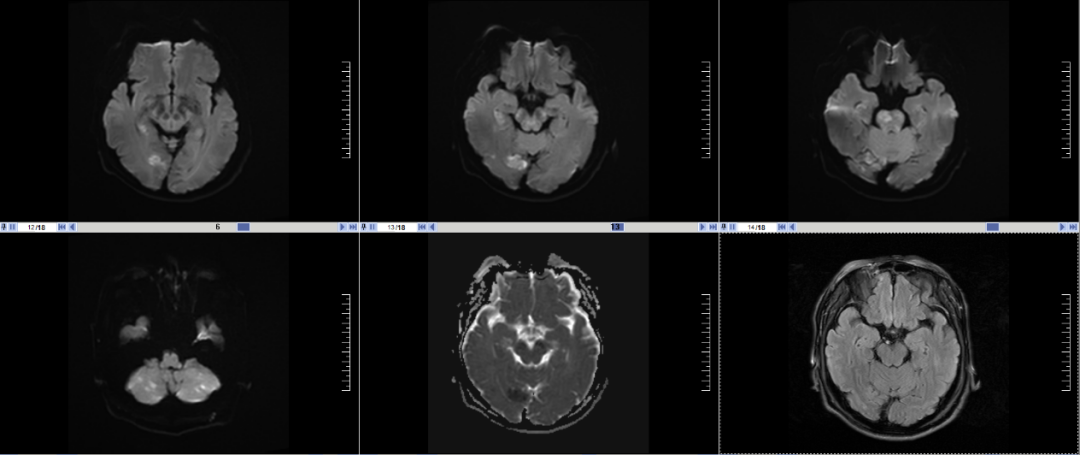

图1 磁共振显示DWI与T2 Flair序列不匹配

神经内科黄圣明大夫认真为患者查体,进行神经功能评估,该患者急查头颅磁共振显示:脑干小脑多发急性脑梗死,基底动脉闭塞。该患者DWI-T2FLAIR序列不匹配,按照指南符合静脉溶栓指征,积极与患者家属沟通病情后,予行静脉溶栓,静脉溶栓后患者病情无明显改善,介入科刘要先主任为患者行“经皮颅内动脉取栓术”,取栓术中可见患者闭塞的基底动脉再通,血供恢复。住院期间经过蔡黎睿医师及黄圣明副主任医师的精心治疗,患者和家属对我院急性脑梗的救治能力给予了很大的肯定!

神经内科主任王明科表示:按照指南,对于醒后卒中,患者磁共振DWI与T2 Flair序列不匹配可以静脉溶栓,椎基底动脉闭塞患者可以发病24小时内介入取栓。